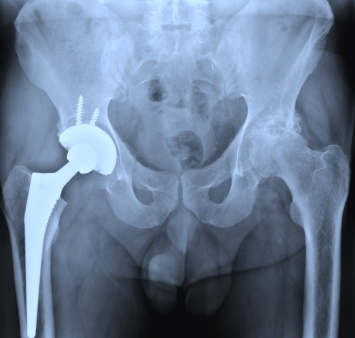

The Dangerous Side of Metal Hip Implants

Attorneys are asking the Food and Drug Administration (FDA) to stop these changes because they say the manufacturer should be held liable for not properly making or warning users about the side effects of metal-on-metal hip implants. Many all-metal hip replacement systems have already been recalled, and the manufacturers are scrambling to offer “new” metal hip implants that may not be any safer, but will get around the recalls.

In addition to the numerous recalls, many metal hip implant victims have also complained that the devices wore down their bones or harmed their organs. Until January 2013, all the manufacturers had to do to get approval was demonstrate that the metal hip implants were similar to the plastic ones already on the market. This, of course, wasn’t the case and it seems like the FDA agrees.

Artificial hip implants become more common in an aging population. If you opted for a metal hip implant thinking it would be sturdier, and you suffered from side effects, you might have a metal hip implant legal claim. There are other victims like you, and you might deserve compensation for your suffering.